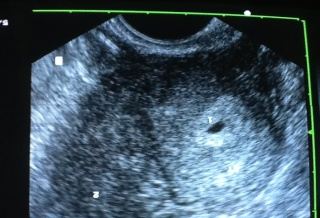

雙子宮雙胞胎 : 博元婦產科 試管嬰兒罕見案例

試管嬰兒罕見案例

蔡鋒博表示,婦人上面的陰道通往左邊子宮,

醫師表示,這實在是非常少見,